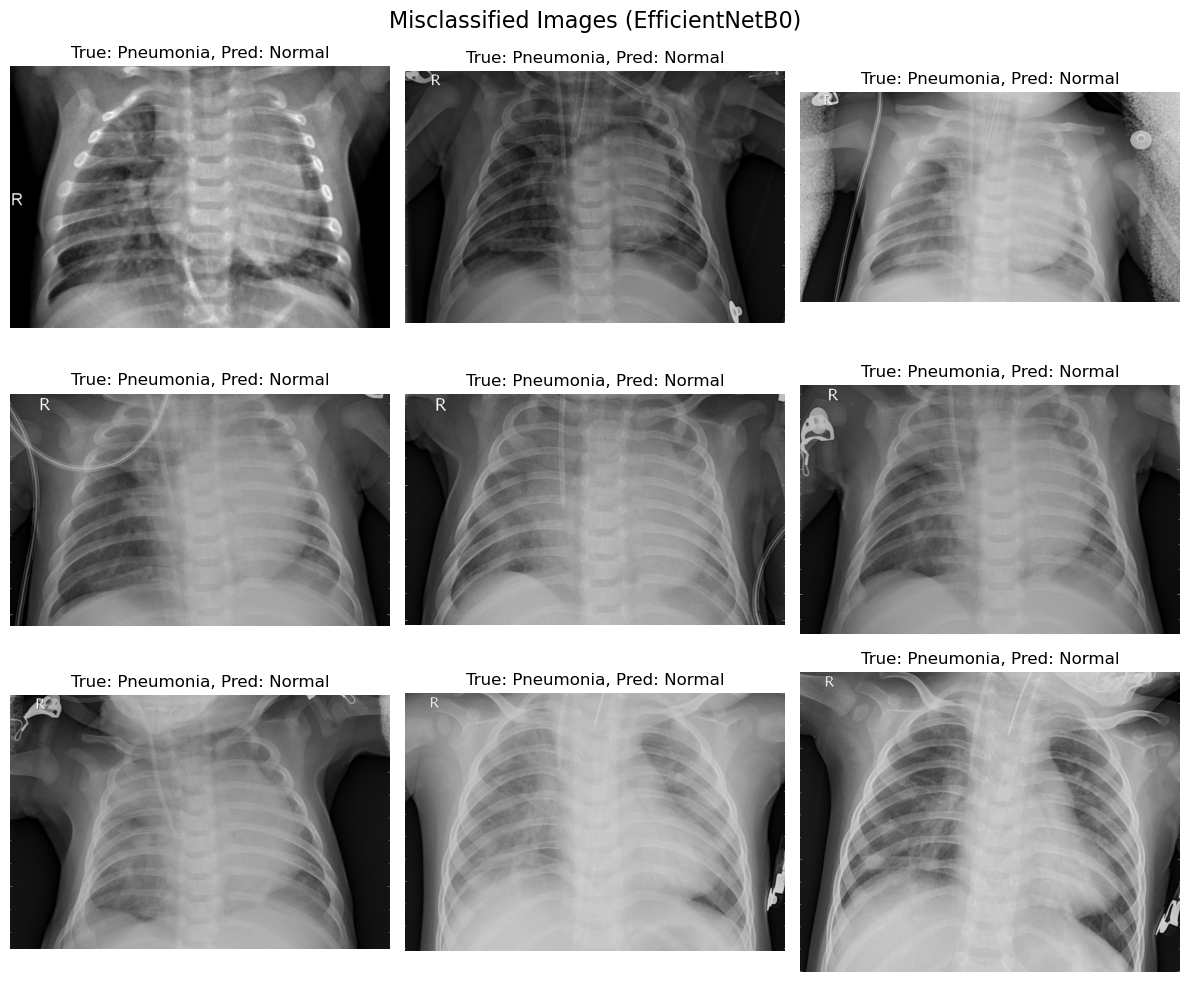

The comparison of the misclassified images from the two models, EfficientNetB0 and ResNet50, provides valuable insights into the strengths and weaknesses of both approaches in diagnosing pneumonia from chest X-ray images.

The confusion matrices and per-class accuracy reveal the following:

EfficientNetB0:

i. Normal Class: Accuracy is low, indicating a high rate of false negatives where pneumonia is classified as normal.

ii. Pneumonia Class: Shows strong recall but at the cost of precision, leading to a slight imbalance in the model’s ability to distinguish between the classes.

ResNet50:

i. Normal Class: Achieved better accuracy for normal cases compared to EfficientNetB0, with fewer false negatives.

ii. Pneumonia Class: Maintained a balanced trade-off between precision and recall, suggesting more reliable generalization.

Model Selection:

i. While both models perform well, ResNet50 is the recommended choice for practical applications due to its ability to minimize misclassifications and provide consistent performance.

i. Misclassifications must be studied in greater detail, as false negatives (pneumonia classified as normal) have significant consequences in clinical decision-making.

ii. A system incorporating ResNet50 with additional interpretability techniques (e.g., Grad-CAM or LIME) could support radiologists in identifying critical cases.

The comparative analysis highlights ResNet50 as the superior model for diagnosing pneumonia, with its deeper architecture enabling better feature extraction and classification performance. However, EfficientNetB0 remains a valuable alternative in scenarios where computational efficiency is a priority. Future work should explore advanced fine-tuning and ensemble methods to further enhance diagnostic accuracy.